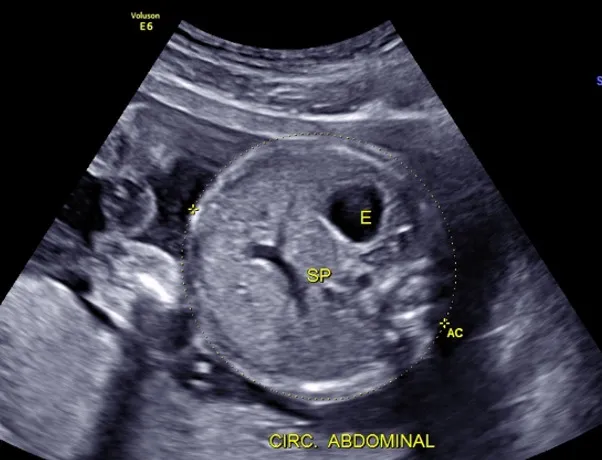

Ultrasonido estructural (entre las 18 y 24 semanas).

Cuando el resultado del estudio de primer trimestre es normal, el siguiente estudio que sugerimos es el Ultrasonido estructural, cuyos objetivos principales son:

- Revisión estructural completa y detallada de la anatomía de bebé para descartar malformaciones.

- Búsqueda de marcadores ecográficos de síndromes genéticos como síndrome de Down. (Sobre todo en pacientes que no se hayan realizado el estudio 11-13.6).

- Evalación de riesgo de preeclampsia.

- Evaluación de riesgo de parto pretérmino.

- Inserción de placenta y líquido amniótico.